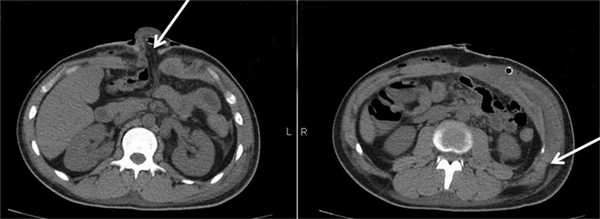

На 6-е сутки после операции выполнена КТ брюшной полости с контрастным усилением (рис. 4): Рис. 4. Компьютерные томограммы органов брюшной полости больного Б. на 6-е сутки после операции. признаки межмышечных и подкожных гематом брюшной стенки с включениями газа, небольшое количество жидкости межпетельно в полости таза, отек подкожной клетчатки поясничной области, контузионные изменения в задних сегментах нижних долей обоих легких (преимущественно правого), перелом крыла левой подвздошной кости.